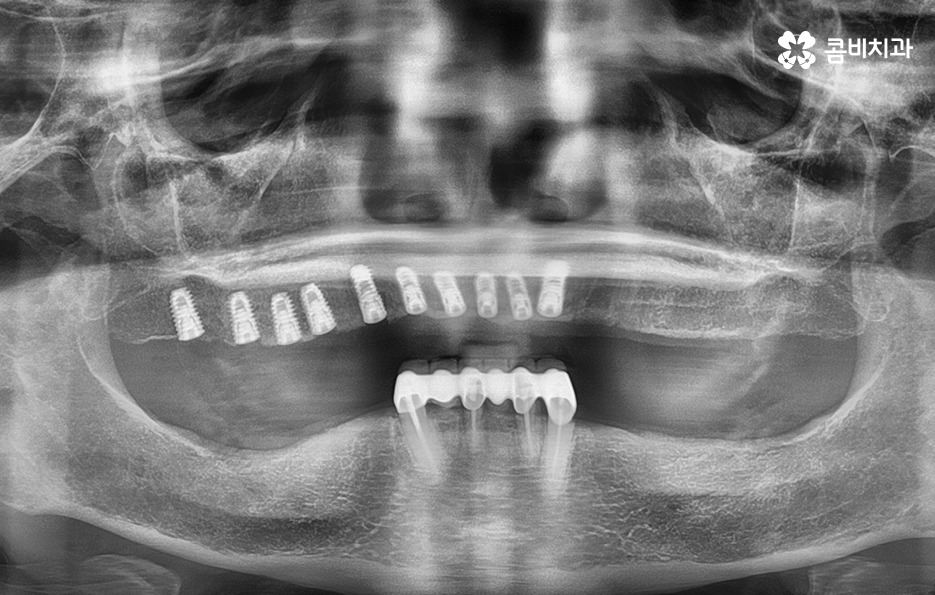

순차적으로 식립이 진행되고 있는 모습

위 사례와 같이 대부분의 치아를 잃게 되신 분들의 경우에는

임플란트가 건강하게 자리를 잡을 수 있도록

시술 과정에 있어서 심혈을 기울여야 합니다.

여러 치아를 잃게 되었을 때 또 한 가지 꼭 유념해야 하는 것은 식립 각도에 따라서 심미적으로

큰 차이가 날 수 있으며 전체적인 교합이

잘 맞물려야 하기 때문에 풍부한 경험과

실력이 필요한 진료에 해당합니다.